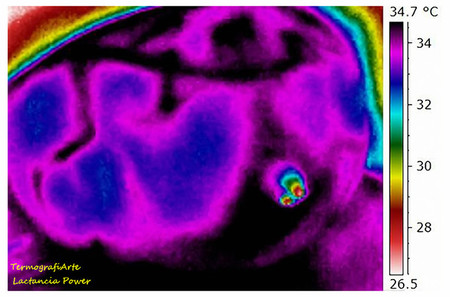

La otra es ésta que tenéis abajo, similar, pero con otra coloración, que se diferencia sobre todo a la anterior por los cambios de temperatura observables en el pezón (en la zona más distal del pezón hay dos puntitos a mucha menor temperatura, que podrían ser gotitas de leche que, ya en el exterior, se han templado un poco). Curioso cuanto menos.